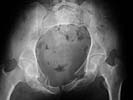

2 days ago I was asked by a local rehab hospital to evaluate a 21 yo female who while visiting out of town was thrown from a walk bridge (fall 20-30 ft). She sustained a left sided lateral compression pelvic ring injury and a fracture dislocation of the left elbow. The injury occurred on 9/1/01 and the treatment of her pelvic injury was skeletal traction and the elbow was splinted only (now subluxed with a comminuted radial head fracture and no motion). Her elbow is a priority a will be addressed.

Probably the best treatment is avoiding this situation. Educate the individuals involved in her initial evaluation. Teach them the importance of clinical and radiographic patient evaluations. Teach them exactly how to examine an injured pelvis. If it had been examined initially, the clinical instability would have been obvious. The radiographs reveal bilateral, comminuted, displaced anterior ramus fractures along with a sacral fracture which violates the anterior, middle, and posterior portions of the sacrum (analogous to a complete sacroiliac dissociation)....a "3 column injury"(if you pretend that the sacrum is a vertebra), so to speak.

Intraoperative fluoro can be misleading regarding deformity corrections...maybe consider plain films when needed. Notice this lady's external rotation of the left hemipelvis postop and its impact on the acetabular coverage...see the inlet(caudal) view with attention to the ischial spine assymetry.